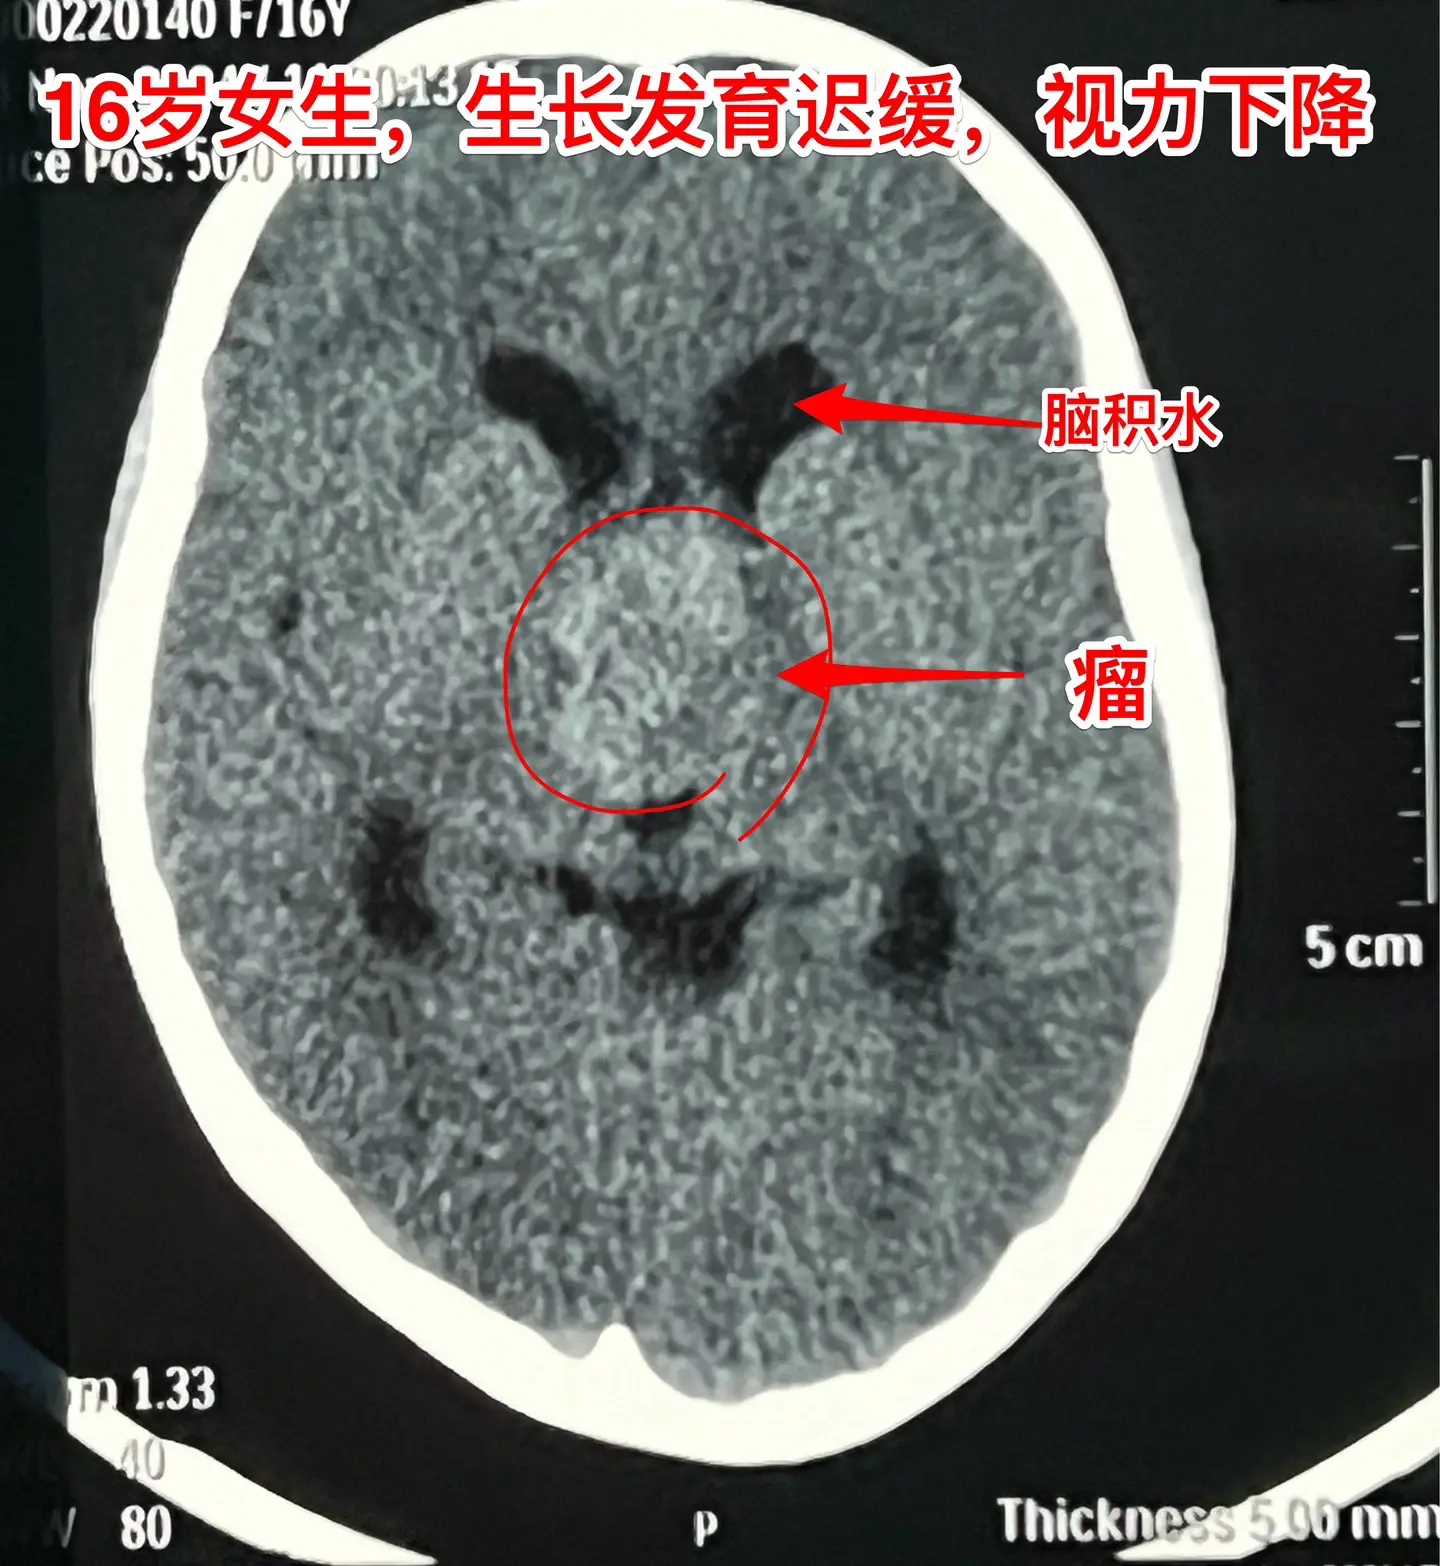

16岁女生在10岁时就有生长发育迟缓症状。16岁衡阳市女生,现在身高才120厘米,体重才21公斤。初中毕业后就辍学了! 她在10岁时就有生长发育迟缓症状,到医院去检查发现生长激素分泌不足。没有找出具体原因,也没有注射生长激素治疗。 近一年有头痛症状,视力也下降了。作磁共振发现长了脑部肿瘤,才到北京来找我作手术。肿瘤体积大,没有钙化,是颅咽管瘤吗? 昨天在手术过程中,取出病变标本作快速冰冻病理检查,报告为乳头型颅咽管瘤。这种类型的颅咽管瘤在小孩子中十分罕见。 我多次提醒家长,如果发现小孩子的生长发育有异常,要尽早到医院去检查,找出原因,尤其是针对脑部要作磁共振检查,排除脑部肿瘤。对于生长激素缺乏者,不能不管原因,轻易注射生长激素治疗。